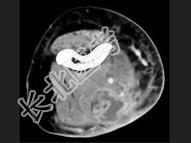

- 单项选择题男,26岁, 肘部红、肿、热、痛,疼痛呈搏动感, 结合图像,最可能的诊断是 ( )

A、脂肪瘤

B、脂肪肉瘤

C、软组织脓肿

D、血管瘤

E、淋巴管瘤